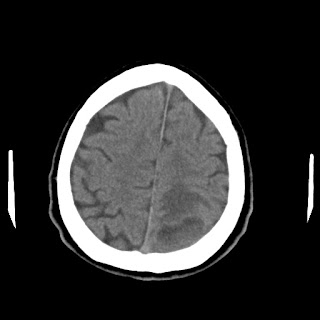

Caso neurorradiología

Paciente de 60 años con cuadro de 1 semana de evolución consistente en tropiezos frecuentes y alteración en la movilidad del miembro

inferior derecho. No refiere

cefalea u otros síntomas asociados, no pérdida de peso, no náuseas o emesis, no

sudoración nocturna. Antecedentes de hipertensión arterial y diabetes.

Escanografía